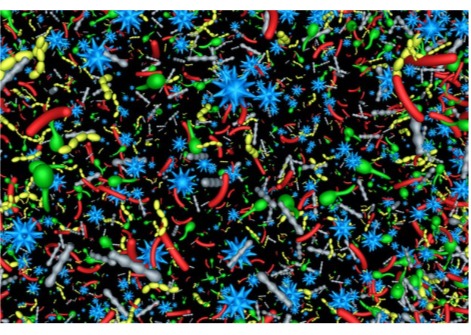

نسيج دماغ بشري مُستأصل، مُجمد بعد 100 مللي ثانية من التحفيز، يُظهر بنيةً داخلية. مقياس الشريط = 100 نانومتر.